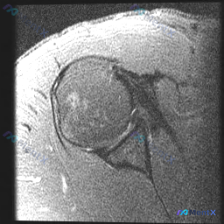

影像序列:肩部MRI T2加权 冠状位

可见结构评估:

- 骨性结构:肱骨头、肩胛盂、肩峰轮廓基本清晰,未见明确骨折、显著骨髓水肿

- 滑囊:肩峰下-三角肌下滑囊未见明显积液

- 盂唇:形态和信号未见明确急性撕裂/分离征象

- 冈上肌腱:肱骨大结节附着处可见明显高信号影